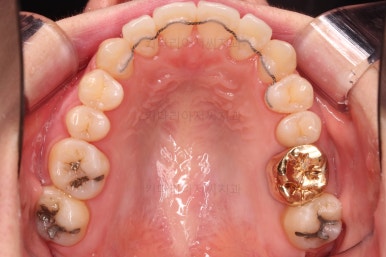

초진 시, 입안의 모습입니다.

좌측 송곳니가 덧니처럼 튀어나가 있고, 송곳니 옆의 작은 억므니가 안으로 쏙 들어가서 덧니 느낌이 더 강조되어 보이네요.

위아래 앞니가 긴밀하게 겹침이 없는 약간의 개방교합(오픈바이트, Openbite) 경향이 보입니다.

웃거나 말할 때 드러나는 치열이 삐뚤어서 심미적으로 좋지 못하고요.